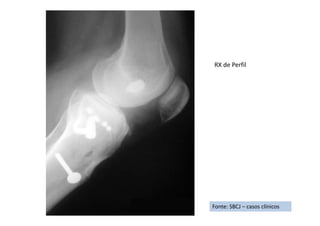

RX de Perfil

Fonte: SBCJ – casos clínicos